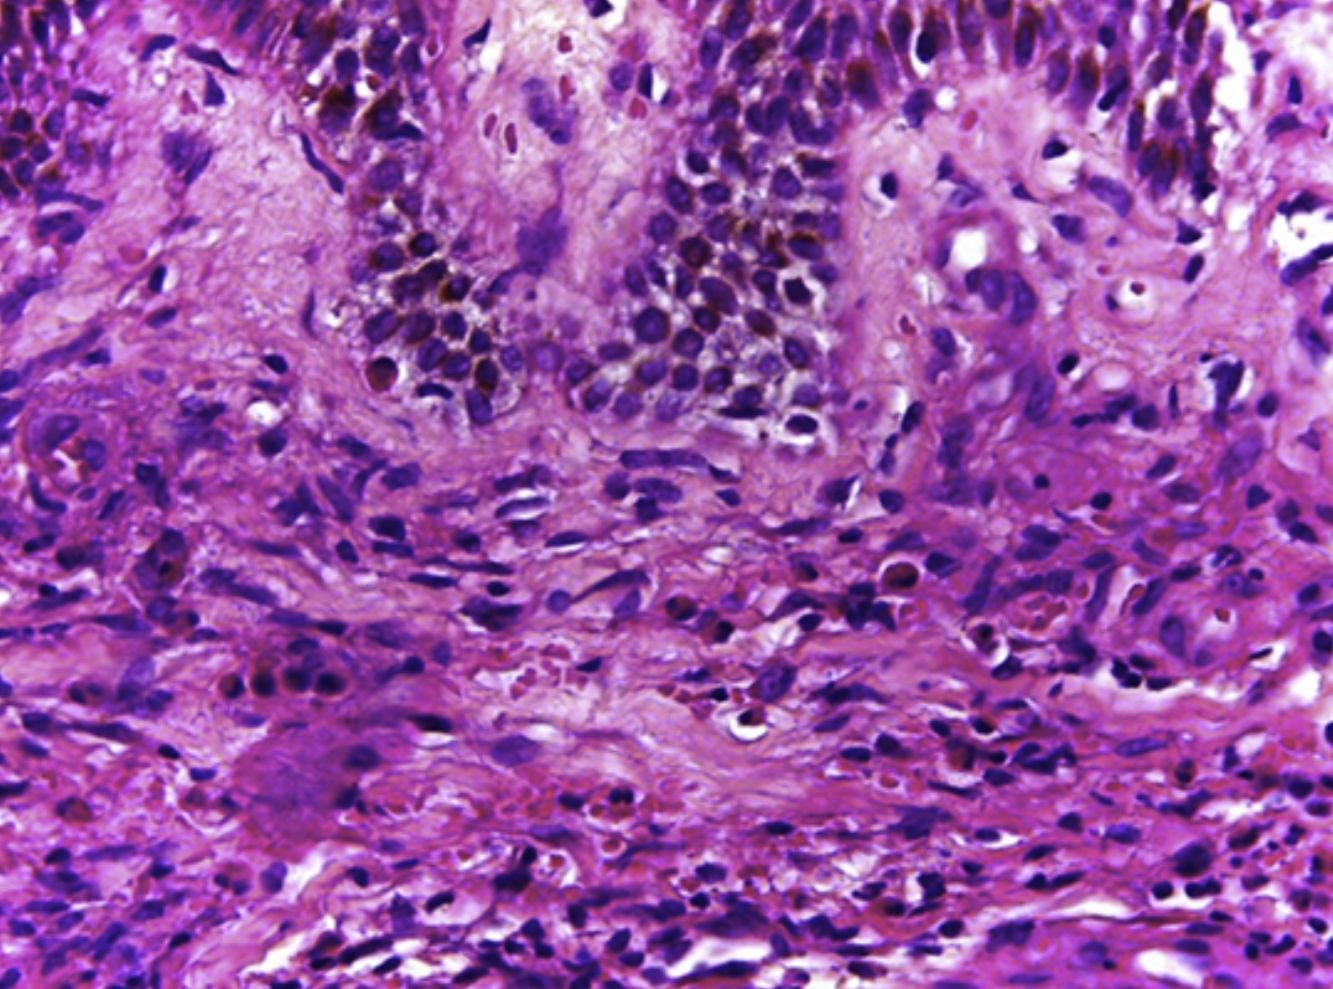

HistologíaLos hallazgos histológicos, descritos por primera vez por Chen et al.1 y repetidos en artículos posteriores, mostraron en todos los casos una vasculitis necrosante de los vasos pequeños de la dermis acompañada de necrosis fibrinoide e infiltrado eosinofílico a lo largo de la dermis con presencia mínima de leucocitoclasia o ausencia de ella (fig. 3a y b). Por lo general, la epidermis es normal excepto por espongiosis eosinofílicas ocasionales1.

| Caso 1 | M/61 | 24 | Generalizada | Bilateral, placas eritematosas purpúricas en miembros inferiores con edema y dolor. Placas purpúricas y dermografismo en rostro, muslos y brazos | Hiperqueratosis y espongiosis. Infiltrado difuso de linfocitos y eosinófilos en la dermis profunda y superficial, y necrosis fibrinoide de los vasos superficiales de la dermis con presencia de abundantes eosinófilos tanto dispersos como invasivos de la pared de los vasos. Sin leucocitoclasia (fig. 2a) | Eosinofilia 0,7×109/L; PCR 13mg/L. Análisis de deposiciones positivo para Giardia lamblia. No hay otras anormalidades significativas (ANCA negativo) | Deflazacort oral 30mg y clobetasol tópico 0,05%. Con la suspensión de los corticoides, los síntomas recidivaron. Mantenida con corticoterapia intermitente tópica y oral | Seis meses sin recurrencia |

| Caso 2 | M/66 | 12 | Miembro inferior | Placa pobremente delimitada, eritematosa purpúrica, en miembro inferior izquierdo. Edema unilateral, picor y dolor | Espongiosis en la epidermis, infiltrado difuso de la dermis superficial y profunda, con necrosis fibrinoide de los vasos de la dermis superficial, y eosinófilos tanto dispersos como invadiendo la pared de los vasos necrosados (fig. 2b) | Eosinofilia 0,4×109/L; PCR 10mg/L, análisis de orina positivo para Escherichia coli. No hay otras anormalidades significativas (ANCA negativo) | Deflazacort 30mg/día y clobetasol tópico 0,05% durante 2 semanas. Con la suspensión de los corticoides, los síntomas recidivaron. Se inició tratamiento con dapsona 100mg/día y deflazacort 30mg/día, reducción de dosis con control de síntomas | Ocho meses sin recurrencia |